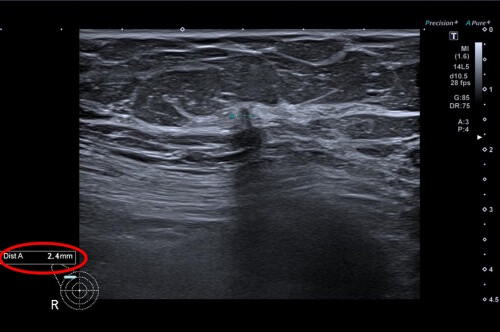

Pilotní projekt využívající umělou inteligenci při vyhodnocování mamografických snímků odstartoval v prvním pololetí 2023 ve spolupráci se zdravotní pojišťovnou OZP a skupinou EUC. Do projektu se jako první zapojilo mamodiagnostické centrum Waltrovka v Praze, které patří mezi nejmodernější v Česku. Vyšetření měly klientky OZP hrazené z fondu prevence jako benefit preventivního programu STOP rakovině prsu.

„Během společného projektu standardně posuzovali každý snímek dva lékaři. Novinkou ale bylo třetí čtení pořízených snímků za pomoci umělé inteligence. Živí odborníci tak získali možnost porovnat svůj nález s doporučením strojového algoritmu, který se učil na milionech snímků uložených v centrální evidenci. Během pilotního projektu jsme si chtěli ověřit, že zapojení AI pomůže snížit riziko přehlédnutí nádorových změn a ulehčí lékařům práci. Podpora a spolupráce s OZP pro nás byla zásadní. Díky ní jsme mohli pacientkám poskytovat vyšetření s využitím AI v běžném provozu a sledovat tak skutečné přínosy i dopady na praxi,“ popisuje prof. MUDr. Jan Daneš, CSc., vysokoškolský profesor a odborník v oboru radiologie a mamodiagnostiky z Mamodiagnostického centra Waltrovka a Beroun, člen skupiny EUC.

Zvýšený zájem o vyšetření se zapojením umělé inteligence při prevenci rakoviny prsu dokládají statistiky loňského a letošního roku Mamodiagnostických center Waltrovka a Beroun. V roce 2024 o něj projevilo zájem 54 % pacientek (celkem 26 481, z toho s využitím AI 14 293), v roce 2025 už se jedná téměř o 74 % (dosud celkem 18 890, z toho AI 13 993). Špičková technologie se tak prakticky během jednoho roku v praxi stala standardem. Lékaři zároveň potvrzují zvýšení záchytu nádorů o zhruba 16,7 %, což odpovídá i výsledkům zahraničních studií.

„Umělá inteligence má mimořádně vysokou přesnost. Negativní prediktivní hodnota dosahuje 99,97 procenta. U naprosté většiny snímků tedy dokáže spolehlivě vyloučit přítomnost nádoru, což snižuje stres a šetří čas pacientek i hodnotitelů,“ popisuje profesor Daneš a doplňuje: „Osobně si nesmírně vážím ještě jedné skutečnosti. Přes počáteční zdrženlivost stoupla důvěra lékařů v technologii během dvou let z 25 % prakticky na 100 %. Dnes už si běžné čtení snímků bez podpory AI neumíme představit.“